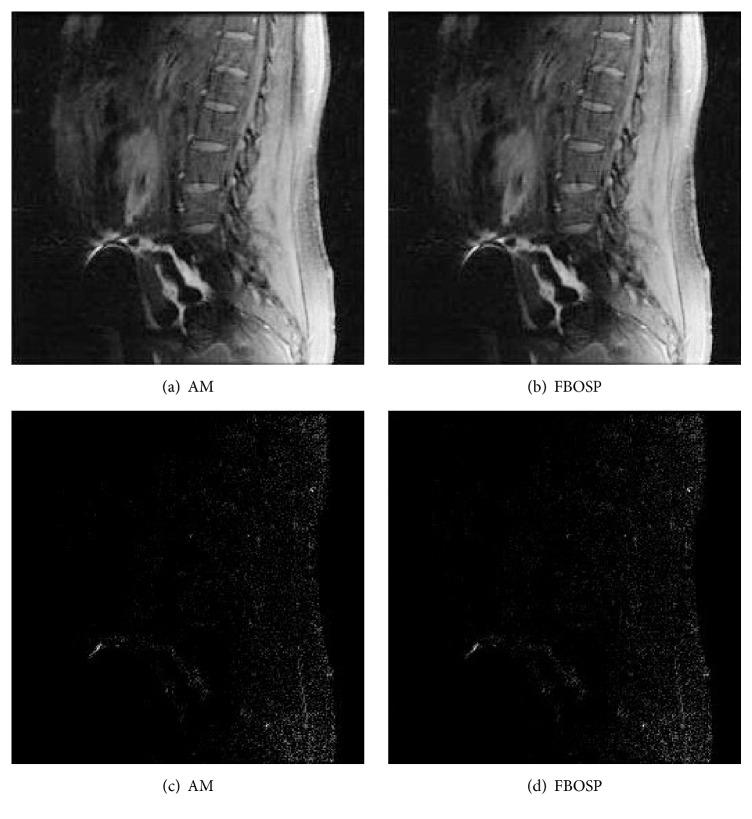

Recently, the sparsity which is implicit in MR images has been successfully exploited for fast MR imaging with incomplete acquisitions. In this paper, two novel algorithms are proposed to solve the sparse parallel MR imaging problem, which consists of regularization and fidelity terms. The two algorithms combine forward-backward operator splitting and Barzilai-Borwein schemes. Theoretically, the presented algorithms overcome the nondifferentiable property in regularization term. Meanwhile, they are able to treat a general matrix operator that may not be diagonalized by fast Fourier transform and to ensure that a well-conditioned optimization system of equations is simply solved. In addition, we build connections between the proposed algorithms and the state-of-the-art existing methods and prove their convergence with a constant stepsize in Appendix. Numerical results and comparisons with the advanced methods demonstrate the efficiency of proposed algorithms.

最近,磁共振(MR)图像中隐含的稀疏性已成功应用于不完全采集的快速MR成像。本文提出了两种新颖的算法来解决稀疏并行MR成像问题,该问题由正则化项和保真项组成。这两种算法结合了前向-后向算子分裂和Barzilai-Borwein方法。从理论上讲,所提出的算法克服了正则化项中的不可微特性。同时,它们能够处理一般的矩阵算子,该算子可能无法通过快速傅里叶变换进行对角化,并确保简单地求解一个良态的优化方程组。此外,我们在提出的算法与现有先进方法之间建立了联系,并在附录中证明了它们在恒定步长下的收敛性。数值结果以及与先进方法的比较证明了所提出算法的有效性。